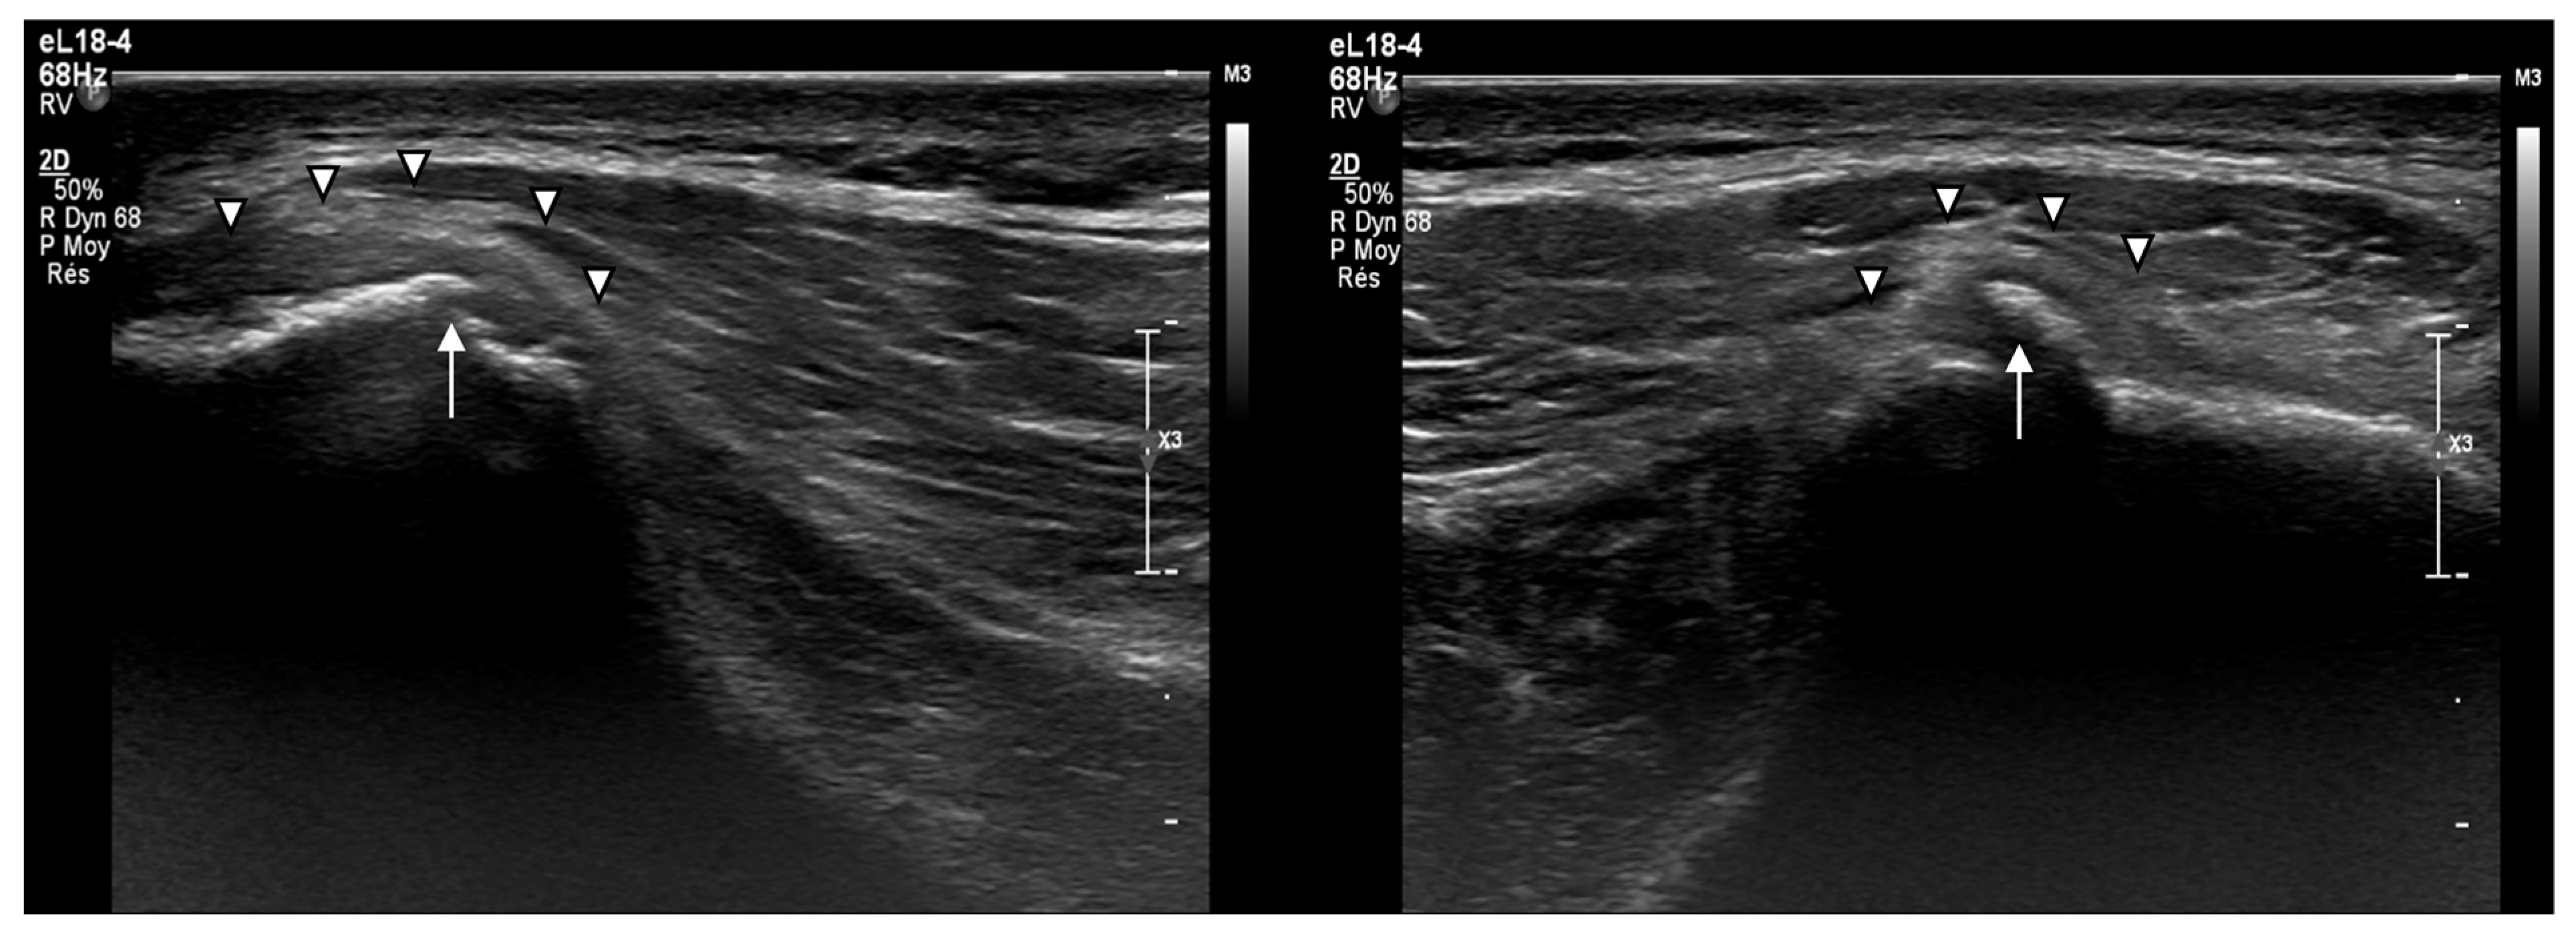

- Subperiosteal hematoma at the posterior iliac crest;

- A 20–25 mm detachment of the gluteus maximus;

- Partial involvement of the gluteus medius.